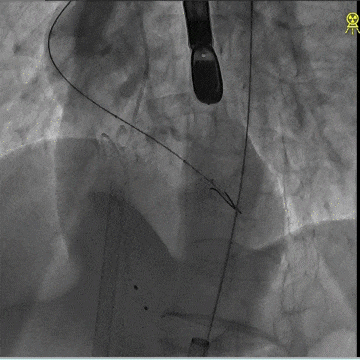

术中造影

瓣膜初始定位